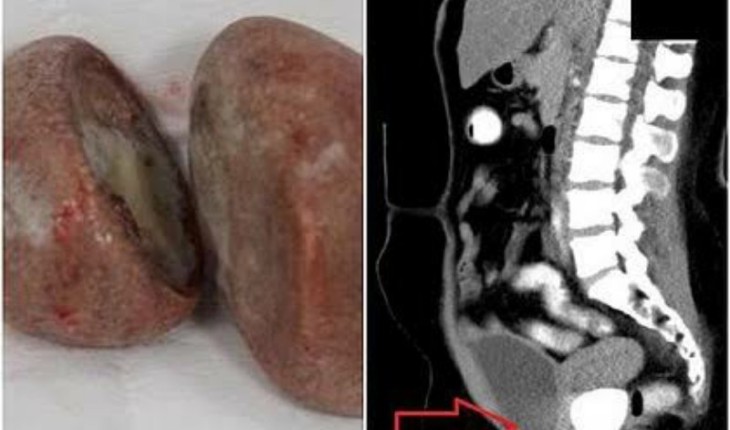

Após a realização dos exames de imagem os dois cálculos foram descobertos instalados dentro da pelve da mulher. Uma das pedras media 3,6 por 5 cm e estava alocada na parede da bexiga e a outra pedra media 5,8 por 5 cm e estava colada na parede do reto.

Os cálculos foram retirados através de cirurgia